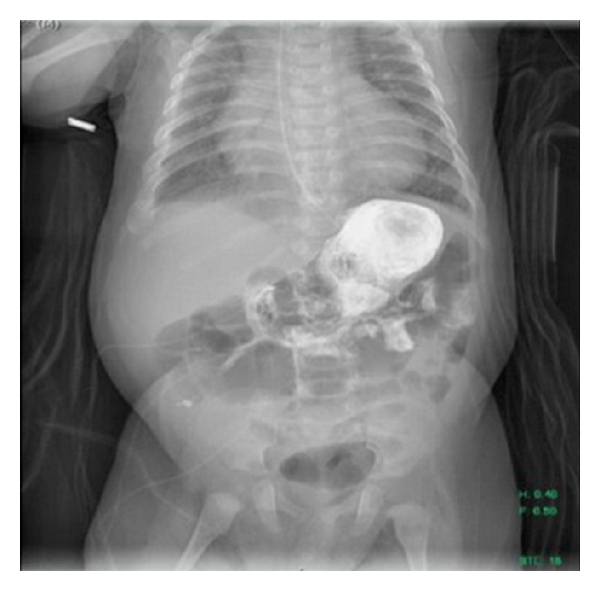

The patient was a 4-month-old full term male hospitalized since birth with a medical history of trisomy 21, congenital hypothyroidism, failure to thrive, pulmonary hypertension, and complete atrioventricular canal defect with repair complicated by chylothorax requiring chest tube drainage who presented with feeding intolerance. He developed feeding issues at day 18 of life requiring initiation of nasogastric tube feeds. A clinical feeding evaluation by Speech Pathology demonstrated severe behavioral feeding challenges and significantly disorganized feeding skills. Due to his history of chylothorax, he was placed on Enfaport, a casein-based formula high in medium chain triglycerides. The formula was also concentrated to 30 kcal/oz secondary to poor weight gain. His underlying cardiac condition required strict fluid management with multiple diuretics. He remained well from a gastrointestinal perspective except for persistent feeding issues. He did not have emesis, diarrhea, constipation, melena, irritability, or increased gastric residuals. He was tolerating his nasogastric tube feeds well. His physical exam was significant for a distended abdomen. His feeding issues continued and he underwent a videofluoroscopic swallow study (VFSS) at 17 weeks of age. The VFSS showed no evidence of aspiration, but there was concern for gastroesophageal reflux disease. An upper gastrointestinal fluoroscopic series demonstrated a large freely mobile intraluminal ovoid filling defect in the gastric body consistent with a GLB (Figure 1). Delayed gastric emptying into the duodenum was also noted on this exam.

Due to concern for adverse outcomes related to the GLB, the decision was made to forgo conservative management and start NAC. Over the course of three days, the patient received 10% NAC at 10 mg/kg/dose diluted in 50 mL of normal saline via nasogastric tube every six hours. The medication was administrated over 30 minutes and the nasogastric tube was clamped for two hours. Gastric contents were aspirated three hours after administration of NAC. Our patient required eight doses of NAC to achieve a clear gastric aspirate. Repeat upper gastrointestinal fluoroscopic imaging demonstrated a complete resolution of the GLB (Figure 2). The infant was subsequently restarted on Enfaport 24 kcal/oz with no further issue or recurrence of the GLB.